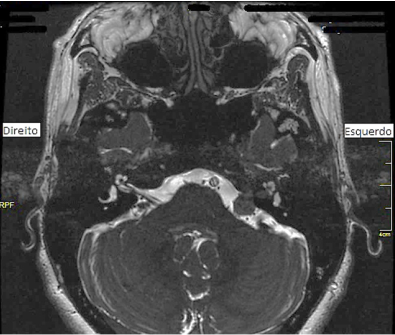

Uma paciente de 75 anos começou a apresentar perda da destreza manual e dificuldade para escrever e fechar os botões das roupas, evoluindo, ao longo de anos, com fraqueza e dormência de membros superiores, predominantemente distal, dor cervical persistente, às vezes intensa, seguida de atrofia de mãos e paraparesia. Foi, então, levada pelos filhos ao médico neurologista e realizou Ressonância Magnética (RM) de crânio, que estava normal, mais Radiografia e RM de coluna cervical, mostradas a seguir. Qual é a principal hipótese diagnóstica para o caso?